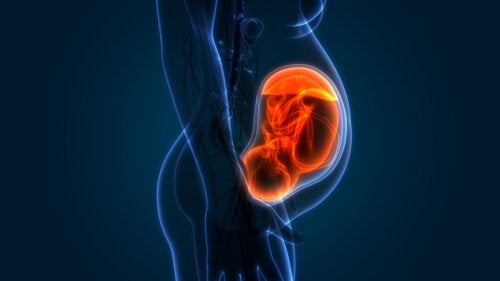

De fases van een zwangerschap

Je lichaam verandert elke week, je baby groeit en er gebeurt nog zoveel meer in je lichaam dan je ooit had verwacht. Een zwangerschap is een ongelooflijk proces, een wonder dat we aan je zullen uitleggen, praktisch en van dichtbij, zodat je volop van deze tijd kunt genieten.